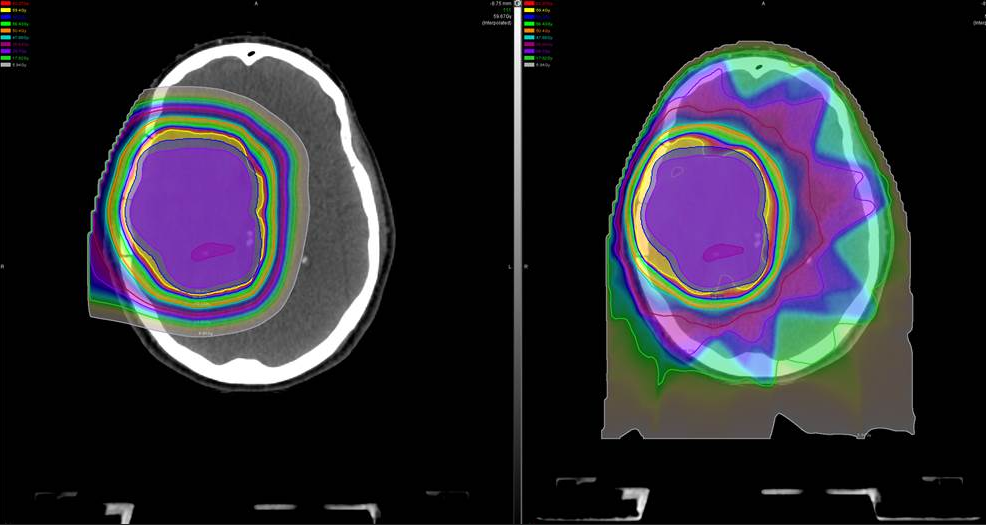

与传统放疗采用光子不同,质子放疗采用的质子能量更高,可以在精确控制下将能量准确地释放到病变部位,对周围正常组织结构损害较小,从而副作用较度降低。

INC国际神经外科医生集团提醒,由于儿童的身体还在生长发育中,放疗可合适缩小甚至消除肿瘤,但传统的光子放疗(X射线)对儿童有潜在的长期副作用,会对生长发育造成损害。例如,0至3岁间是幼儿大脑发育的黄金时期,越小接受放疗,5年内智力损伤的幅度越大。而质子治疗则为广大脑瘤儿童家长提供了一种理想的选择,可在合适杀灭肿瘤的同时,将副作用降到较低。质子的辐射可以较大限度降低对正常组织的伤害,对目标肿瘤细胞造成尽可能多的损害。以儿童髓母细胞瘤为例,我们可以看到普通放疗产生的大部分副作用,质子都的规避了。